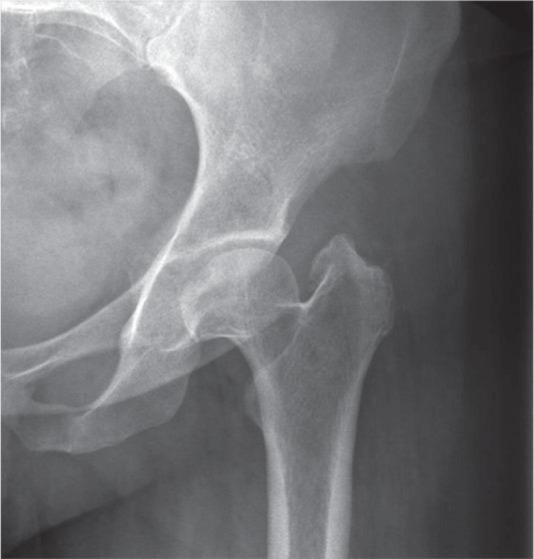

In this review, we bring to the attention of the reader three relatively unknown types of hip impingement. We explain the concept of low anterior inferior iliac spine (AIIS) impingement, also known as sub-spine impingement, ischio-femoral impingement (IFI) and pelvi-trochanteric impingement. For each type of impingement, we performed a search of relevant literature.We searched the PubMed, Medline (Ovid) and Embase databases from 1960 to March 2016. For each different type of impingement, a different search strategy was conducted.In total, 19 studies were included and described. No data analysis was performed since there was not much comparable data between studies.An overview of symptoms, clinical tests and possible surgical treatment options for the three different types of extra-articular impingement is provided.Several disorders around the hip can cause similar complaints. Therefore, we plead for a standardized classification. In young and athletic patients, in particular, there is much to gain if hip impingement is diagnosed early. Cite this article: 2018;3:30-38. DOI: 10.1302/2058-5241.3.160068.